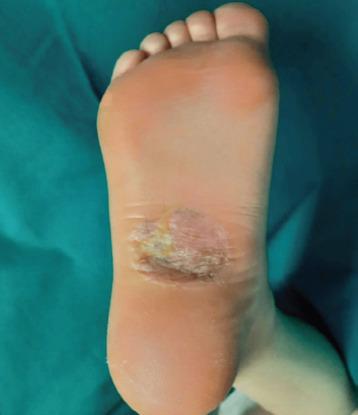

CASE PRESENTATION

Here is a case report of a 27-year-old woman diagnosed with a hidradenocarcinoma over a previously excised hidradenoma in the right foot. The diagnosis was made after right pelvic and inguinal lymphadenopathies appeared few months after a new small asymptomatic lump appeared at the same place in the sole of the right foot were the excised hidradenoma five years before was located. Lymph node biopsy was performed, with histopathological diagnosis of hidradenocarcinoma metastasis. Surgical local wide excision of the lump at the foot and lymphadenectomies was performed. Histopathological analysis of the samples confirmed the diagnosis of hidradenocarcinoma. The patient later received adjuvant radiotherapy and after one year there are no signs of disease recurrence.

本文报告一例27岁女性病例,其在先前切除的右脚汗腺腺瘤上被诊断为汗腺癌。诊断是在右脚足底原切除汗腺腺瘤的部位出现一个新的无症状小结节数月后,右侧盆腔和腹股沟淋巴结肿大时做出的。进行了淋巴结活检,组织病理学诊断为汗腺癌转移。对足部肿块进行了手术局部广泛切除及淋巴结清扫。样本的组织病理学分析证实了汗腺癌的诊断。患者随后接受了辅助放疗,一年后无疾病复发迹象。